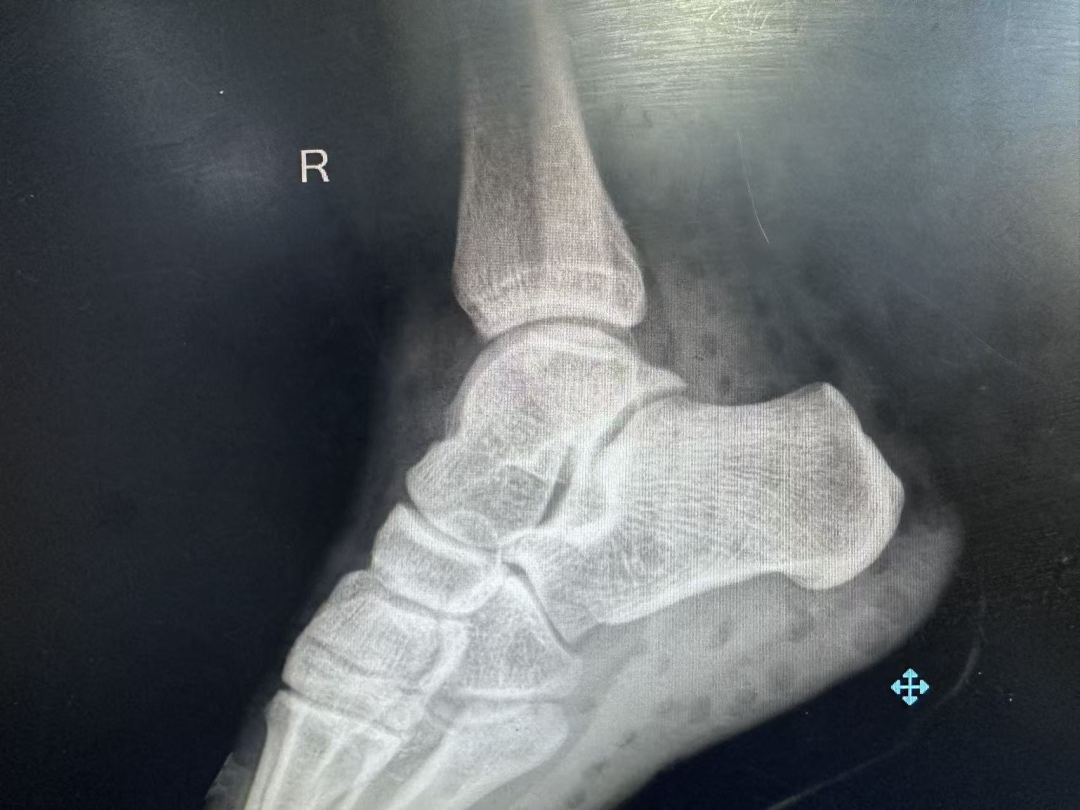

踝关节侧位片

术前影像学检查